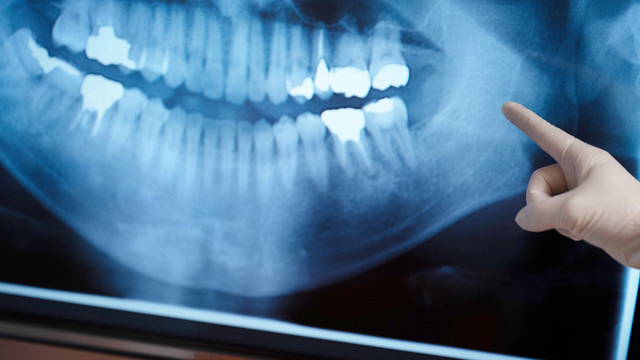

当院のなるべく神経を残す治療

鹿児島市・鹿児島でなるべく神経を残す治療なら、「毛利歯科クリニック」へお任せください。

上述のように、歯の神経をとってしまうとさまざまなデメリットを招きます。そうならないためにも、当院ではなるべく健康な歯質を削らず、神経を残せる可能性を高めています。

虫歯治療では、虫歯に感染している部分を削る際、健康な歯質も削られてしまうケースが少なくありません。当院ではさまざまな工夫を重ね、なるべく健康な歯質を削らずに済むよう努めています。